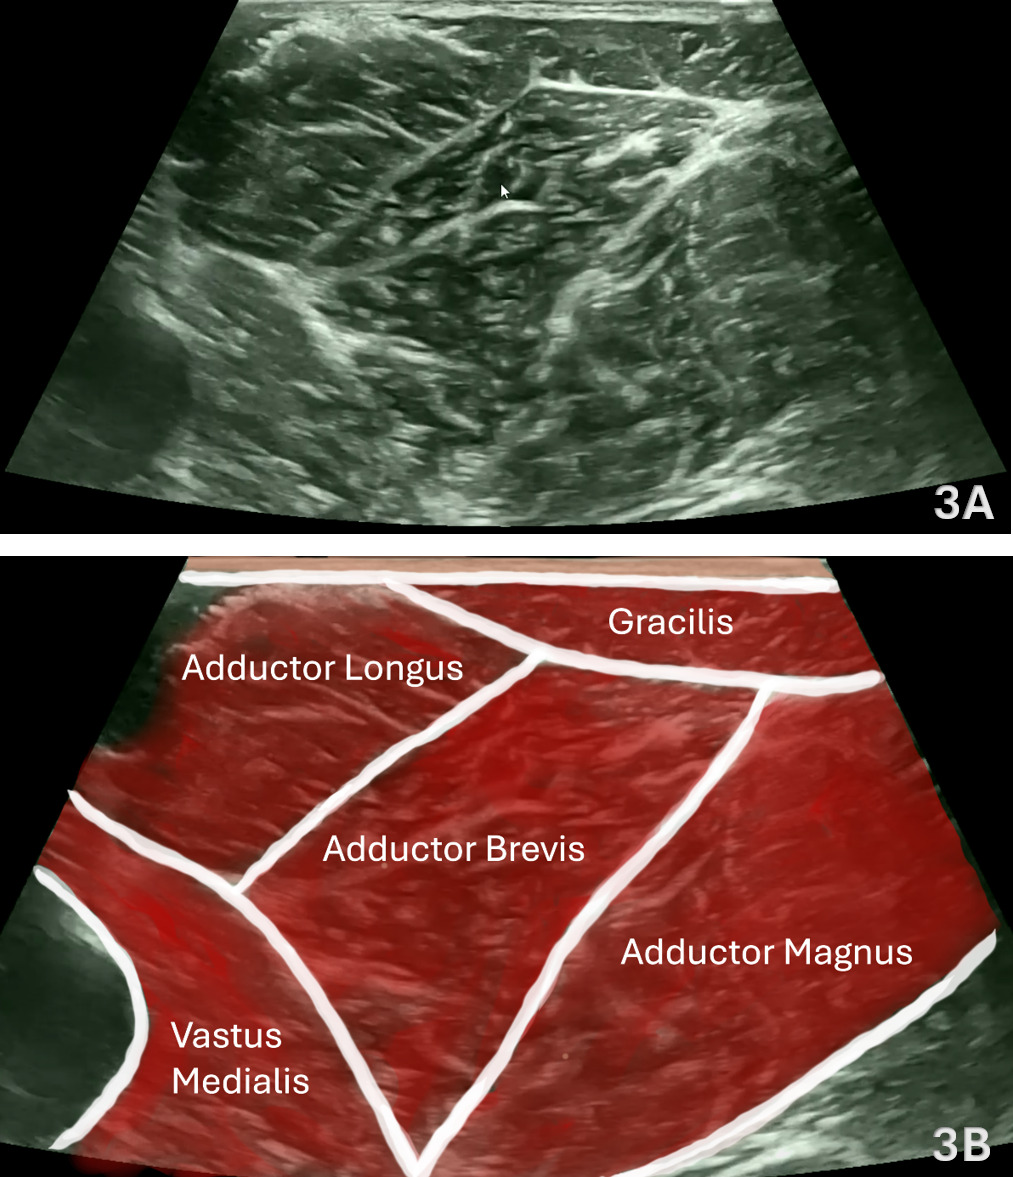

Figures 3A and 3B: Normal Adductor Longus in SAX

Refer to Figure 1C for the transducer position for this image. In SAX, position the transducer transversely just posterior to the adductor longus tendon and center over the muscle belly. The gracilis serves as a consistent superficial and medial landmark, with the adductor longus positioned deep to it, and the adductor brevis and adductor magnus lying deeper and more posterior—forming the characteristic layered appearance of the medial thigh (gracilis → longus → brevis → magnus). The intramuscular tendon of the adductor longus may be seen centrally as an oval echogenic structure surrounded by hypoechoic muscle tissue. Use light transducer pressure to avoid compression artifacts and maintain consistent depth and contrast. Sweep proximal ↔ distal along the muscle to evaluate continuity from the pubic attachment through the myotendinous junction and into the distal belly. Apply gentle probe toggling to minimize anisotropy, particularly near the tendon, ensuring that echogenicity accurately represents fiber alignment. Document tendon thickness, echotexture, and continuity bilaterally for comparison, noting any focal hypoechogenicity, loss of definition, or asymmetry that may indicate tendinopathy or partial tearing.